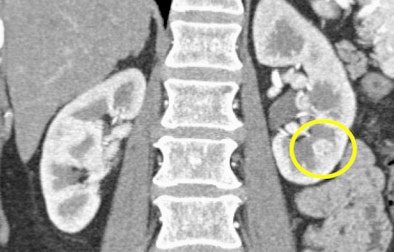

CT images from a patient with transitional cell carcinoma (TCC) were also best appreciated in late-phase imaging. The early-phase data showed slight differential diffusion between the right and left kidneys and a subtle lower-density region in the right kidney. With excretory-phase imaging, the TCC was visible in the axial view and was even more clearly defined in the coronal view.

| In a patient with TCC, slight perfusion differences can be seen between the right and left kidneys in the arterial phase (above), and a subtle lower-density zone can be appreciated in the right kidney. On excretory-phase imaging, in both the axial view (below) and coronal view (bottom) it becomes an obvious infiltrative tumor. |